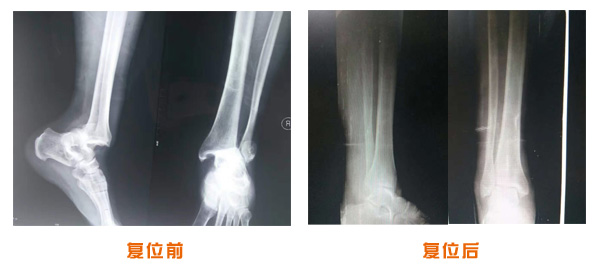

肘關節脫位骨折治療前后對比

踝關節脫位骨折治療前后對比